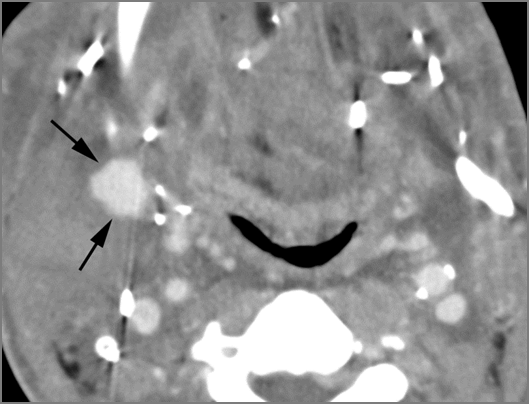

There is reactive cervical lymphadenopathy. [Yes/No]

There is suppurative cervical lymphadenopathy. [Yes/No]

If there is suppurative cervical adenopathy the purulent material outside the lymph node(s) capsule(s). [Yes/No]